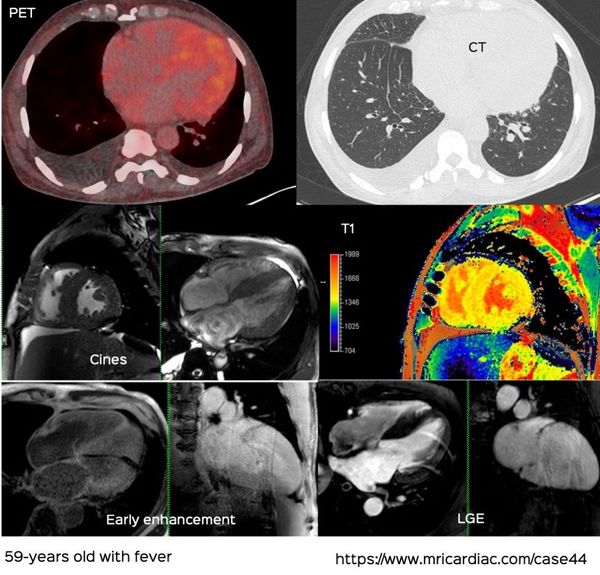

Cardiac MRI is a useful tool to diagnose amyloidosis. T1 mapping has become a mainstay, both native and ECV measurements. ECV measurement can now help quantify the amyloidosis burden and may help guide treatment based on how the ECV responds to specific treatment measures.

It is not just cardiac MRI and cardiac CT that give us clues to a cardiac pathology. We should look at the heart on any cross-sectional thoracic study.